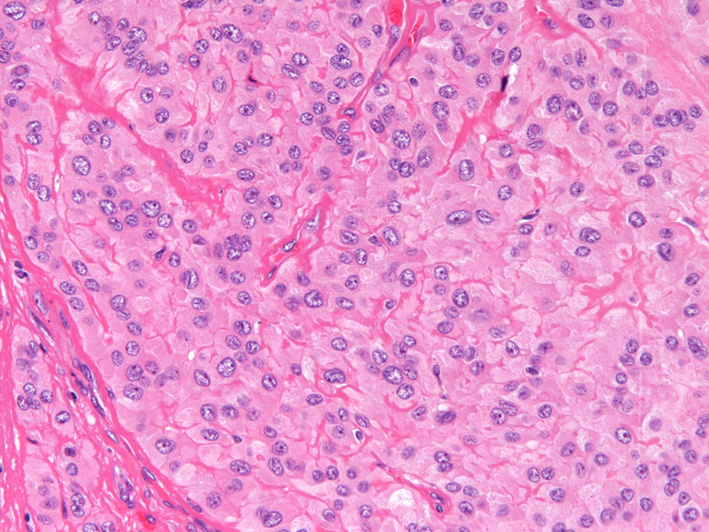

腫瘍は好酸性細顆粒状の豊富な胞体を有した比較的均一な細胞の胞巣状充実性増殖からなっている(HE染色,対物x20). |